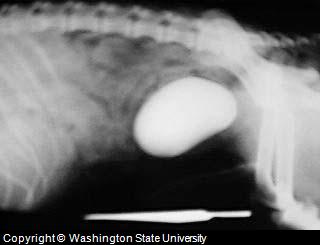

Bladder Stone X-Ray

This

dog was admitted to the veterinary hospital with hematuria (blood

in dog urine), dysuria (difficult or painful dog urination)..

X-Ray and ultra-sound examination revealed an enormous canine urinary

bladder stone.

Source: Washington State University